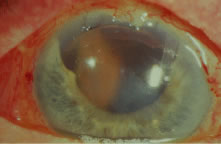

Diagnosis and Classification An extensive description of the diagnosis and classification of the angle-closure

glaucomas cannot be given here.1,43 However, the essential component in the diagnosis of the angle-closure

glaucomas, gonioscopy, must be mentioned. Differentiation between optical

contact and actual adhesion between the iris and the cornea cannot

be made without the use of indentation gonioscopy; therefore, the correct

diagnosis of the angle-closure glaucomas demands the appropriate

use of a gonioscopic lens that can be used in indentation gonioscopy8,44 (Fig. 9). We prefer the Zeiss four-mirror lens on an Unger handle. For the diagnosis

of angle-closure glaucoma to be certain, the ophthalmologist must

be certain that the symptoms could only be the result of angle closure

and that the anterior chamber angle actually has closed. Thus, the

search for peripheral anterior synechiae, characteristically between

the 10 and 2 o'clock positions of the eye, assumes great significance.  Fig. 9. Indentation gonioscopy. A. The angle appears closed. However, the observer cannot determine whether

this appearance is due to mere contacts between the iris and cornea

or to actual adhesion. B. The goniolens has been pressed against the central cornea, displacing

aqueous into the periphery and showing that the angle is open. C. Indentation gonioscopy displaces the iris posteriorly, showing peripheral

anterior synechiae. (Schwartz LW. Diagnostic evaluation of the patient. In Spaeth GL (ed). Early

Primary Open-Angle Glaucoma: Diagnosis and Management. Boston: Little, Brown & Co, 1979.) Fig. 9. Indentation gonioscopy. A. The angle appears closed. However, the observer cannot determine whether

this appearance is due to mere contacts between the iris and cornea

or to actual adhesion. B. The goniolens has been pressed against the central cornea, displacing

aqueous into the periphery and showing that the angle is open. C. Indentation gonioscopy displaces the iris posteriorly, showing peripheral

anterior synechiae. (Schwartz LW. Diagnostic evaluation of the patient. In Spaeth GL (ed). Early

Primary Open-Angle Glaucoma: Diagnosis and Management. Boston: Little, Brown & Co, 1979.)